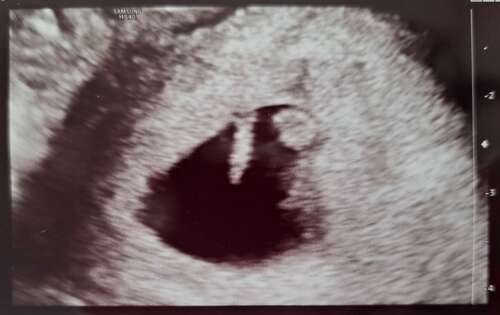

Vandaag eerste echo gehad 5weken 4dagen vruchtzakje met vruchtje en klein knipperend hartje

Gister de eerste echo gehad met 6+3 met al een heel mooi kloppend hartje 馃槏

Afgelopen maandag met precies 6 weken. De vruchtzak had ook precies de grootte van 6 weken. Een mooi kloppend hartje al gezien. 馃グ